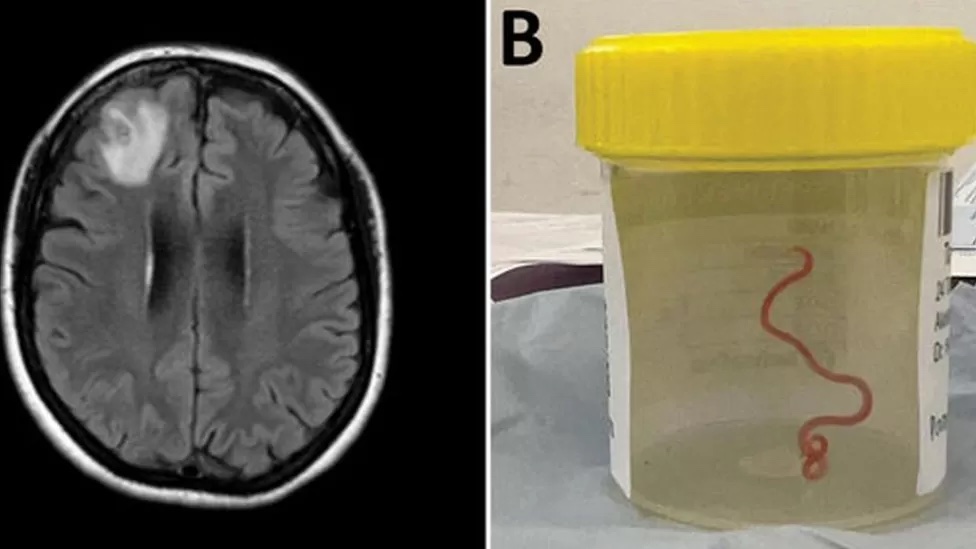

a brain scan and the worm in a jar. Photo BBC

Scientists said an 8cm (3in) worm has been found alive in the brain of an Australian woman, in what is said to be the first of such discovery in the world.

The “string-like structure” was pulled from the England-born patient’s damaged frontal lobe tissue during surgery in Canberra last year.

The red parasite could have been there for up to two months, according to a BBC report.

The patient was admitted to hospital in late January 2021. A scan later revealed “an atypical lesion within the right frontal lobe of the brain”. The cause of her condition was only revealed by a surgeon’s knife during a biopsy in June 2022.